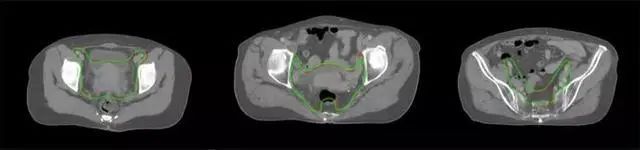

技術原理

基于深度學習人工智能的放療靶區(qū)智能勾畫技術和自動計劃技術,基于全面的市場調研和臨床專業(yè)意見,采用獨創(chuàng)的基于小樣本量的人工智能算法,實現(xiàn)放療靶區(qū)和危及器官的快速全自動勾畫。

產(chǎn)品優(yōu)勢

縮短至幾分鐘內便可完成,大幅提升了放療效率,且人工智能平臺完成的靶區(qū)勾畫可基本滿足臨床醫(yī)生需求,專家只需審核時細微調整,可顯著提高靶區(qū)勾畫的規(guī)范化及精準度,讓放療智能化,標準化??筛采w食管癌、鼻咽癌、直腸癌、宮頸癌、肺癌等多種病種。